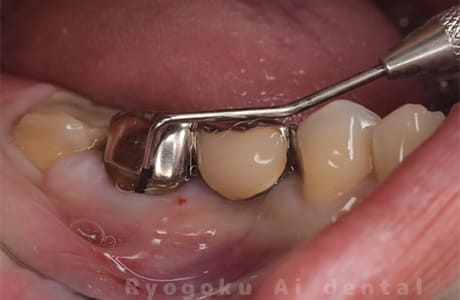

Case12

- 原因

- 左下7番歯牙破折

-

- 治療内容

- インプラント治療

- 治療費用

- 約600,000円

左下の奥歯が痛いとのことでご来院された患者様です。歯が完全に割れており、保存が不可能であったため、抜歯を行い、その際に骨に変わるお薬を入れ、十分な治癒を待ってからインプラント治療を行いました。経過良好で、大変満足されました。

<リスク・副作用>

治療後、痛みや違和感、出血、腫れなどが出る事があります。喫煙者、糖尿病などの方の場合、歯が生着しない場合があります。